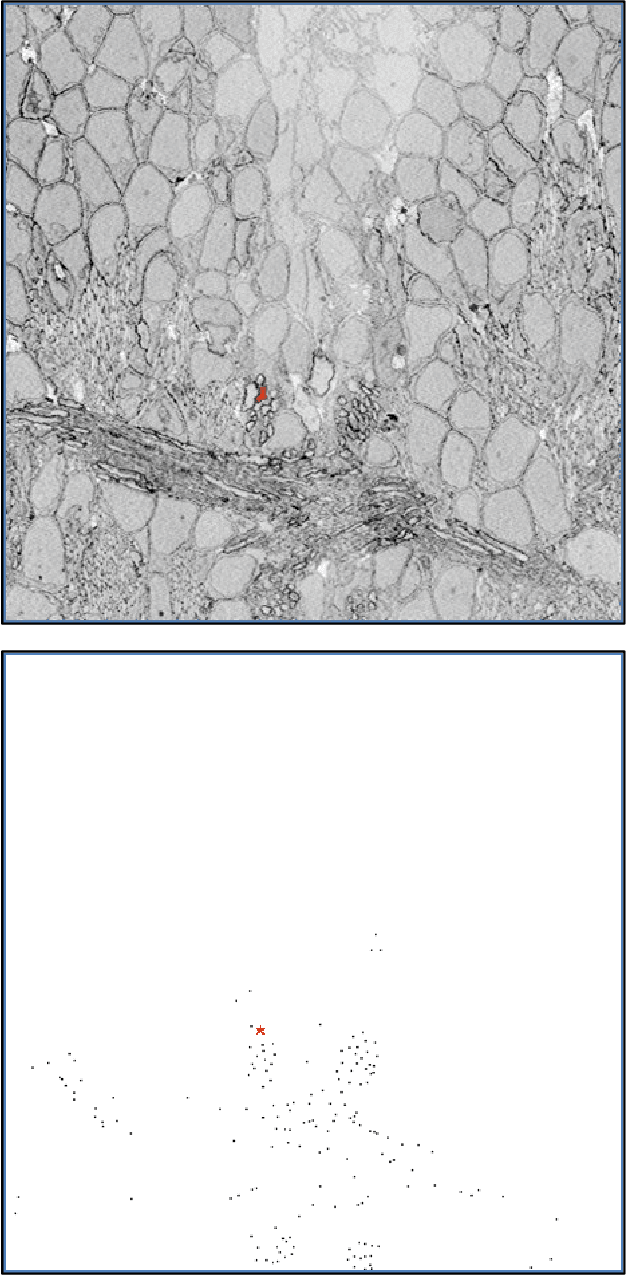

Abstract:The tracing of neural pathways through large volumes of image data is an incredibly tedious and time-consuming process that significantly encumbers progress in neuroscience. We are exploring deep learning's potential to automate segmentation of high-resolution scanning electron microscope (SEM) image data to remove that barrier. We have started with neural pathway tracing through 5.1GB of whole-brain serial-section slices from larval zebrafish collected by the Center for Brain Science at Harvard University. This kind of manual image segmentation requires years of careful work to properly trace the neural pathways in an organism as small as a zebrafish larva (approximately 5mm in total body length). In automating this process, we would vastly improve productivity, leading to faster data analysis and breakthroughs in understanding the complexity of the brain. We will build upon prior attempts to employ deep learning for automatic image segmentation extending methods for unconventional deep learning data.